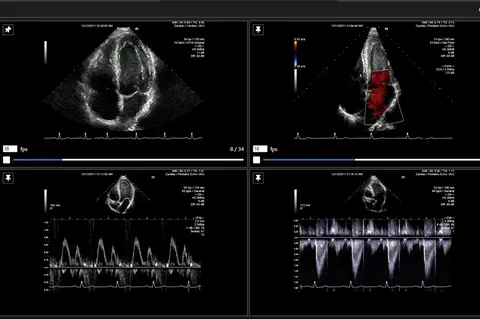

L'essai multicentrique international FAST II confirme la haute précision diagnostique de la solution CAAS vFFR de Pie Medical Imaging

PRNEWSWIRE, le 19/05/2021 : MAASTRICHT, The Netherlands, 19 mai 2021 /PRNewswire/ -- Pie Medical Imaging (« PMI »), un leader mondial de l'imagerie cardiaque, a annoncé aujourd'hui la conclusion de l'essai FAST II et la présentation des résultats en tant qu'essai clinique de dernière minute à l'EuroPCR 2021. […].